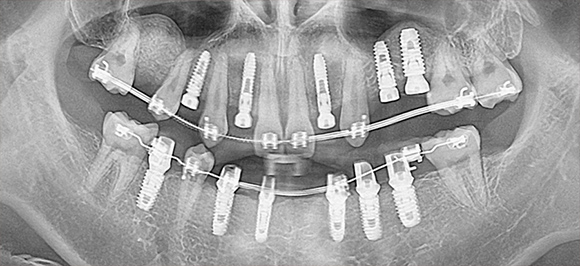

상악동 임플란트는 치과치료 중 난이도 높은 임플란트

윗 턱뼈와 코가 연결된 빈 공간을 확보하여 활용

윗니(좌·우 양쪽 치아) 임플란트 진행 시, 뼈이식과 함께 진행